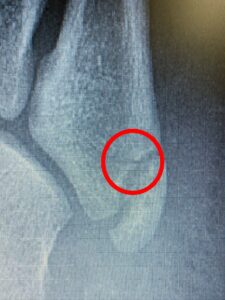

けど、第五中足骨の骨頭を触れると明らかに他の部位とは違う反応が❗️

結果、折れてました😅

CA635E37-EDE4-4CEF-8475-909A8FF544AE 85171FEB-0DD0-433A-A7F5-8381FAB181D9

この骨折、いわゆる下駄骨折って言って下駄履いて転んだらよくなるやつなんです❗️